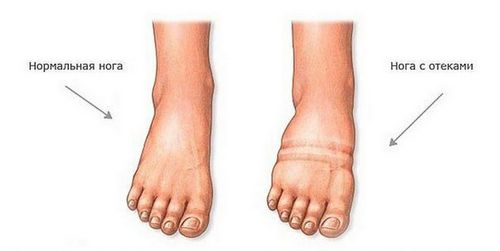

Навіть легка пастозність привертає до себе увагу і помітна неозброєним оком. Шкіра стає більш гладенькою, спостерігається невелике збліднення і зменшення еластичності. Візуально вона виглядає натягнутою.

Найчастіше набряклість ніг помітна по взуттю, яка стає тісній і одягається насилу, навіть шкарпетки залишають яскравий слід. Ноги «наливаються» і значно збільшуються в розмірі. Відбувається це завдяки силі гравітації і тривалого перебування у вертикальному положенні. Ноги швидко втомлюються, відчувається тяжкість.

Якщо візуально наявність набряків кінцівок викликає сумнів, в домашніх умовах найлегше перевірити свої побоювання за допомогою легкого натискання одним пальцем руки на нижню передню частину гомілки, в тому місці, де відсутня м'язова тканина. При наявності зайвої рідини, на шкірі повинна з'явитися невелика бліда «ямка».

Існує спеціальна шкала, за допомогою якої визначається ступінь тяжкості протікає процесу. Залежить вона від того, як глибоко деформується при натисканні шкіра, і наскільки швидко повертається до нормального стану.

Розрізняють 4 ступеня тяжкості:- 0-2 мм, западина ледь помітна і зникає майже миттєво,

- 2-4 мм, не сильно виражене поглиблення, зникає через 10-25 секунд,

- 4-6 мм, ямка добре помітна, а ноги виглядають налитими,

- 6-8 мм, сильно виражене поглиблення, не проходить протягом 2-5 хвилин, дуже розпухлі кінцівки.